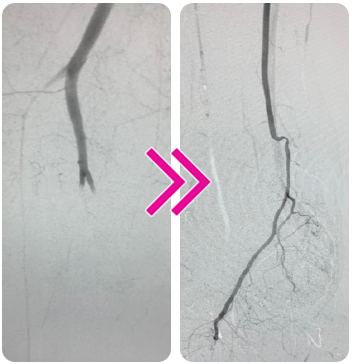

Successful Removal of Acute and Organized SFA Thrombus in One Pass With the Pounce™ Thrombectomy System

Vince Weaver, MD

A 45-year-old man presented with sudden left leg pain that had persisted for 1 week. The patient had a prior history of embolic and thrombotic events, including left common femoral artery (CFA) bifurcation embolus requiring open embolectomy and, 1 year later, percutaneous thrombectomy of the ostium of the superficial femoral artery (SFA).